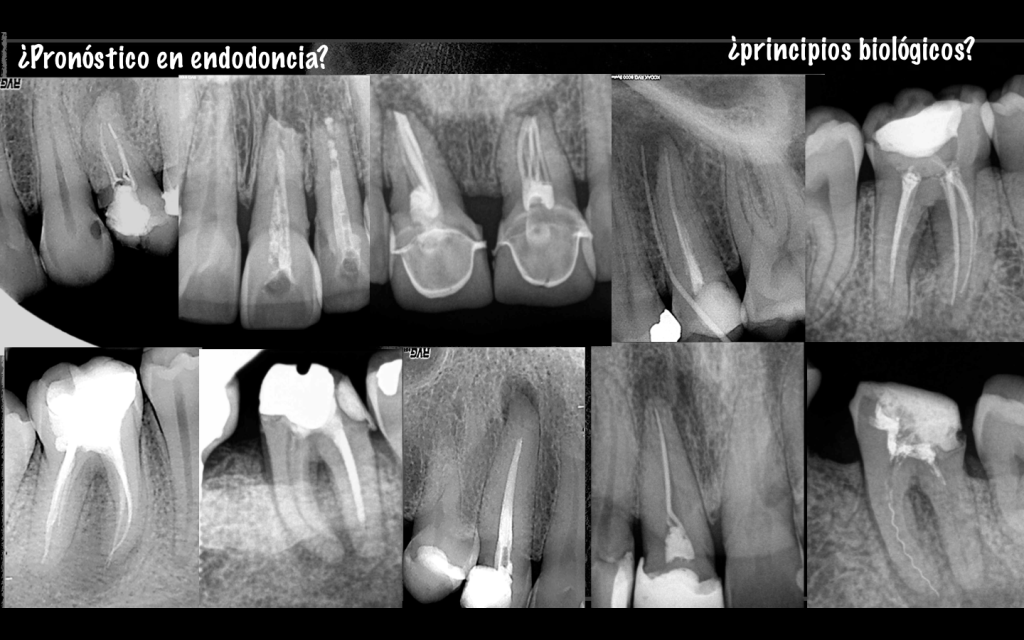

Este fin de semana he tenido el privilegio, a pesar de lo mal que se pasa, de poder hablar de «Pronóstico en Endodoncia» en el Simposium de AEDE, sé que puede ser un tema muy discutido en cuanto a porcentajes, lo cual considero, como ya comenté, que depende de muchísimas variables (factores preoperativos, intraoperativos y postoperativos), los cuales sería muy complicado desarrollar aquí.

Pero este post, es para mostrar que en términos generales , EL TRATAMIENTO DE ENDODONCIA ES UN TRATAMIENTO MUY PREDECIBLE, siempre que se cumplan los requisitos biológicos de : desinfección y obturación del sistema de conductos.

Así pues, ¿realmente estos casos cumplen esos requisitos?, ¿podríamos hablar de éxito o fracaso de estos tratamientos ?…. no se consideran tratamientos de endodoncia, con lo que no podríamos meterlos en el saco de «Pronostico en endodoncia».